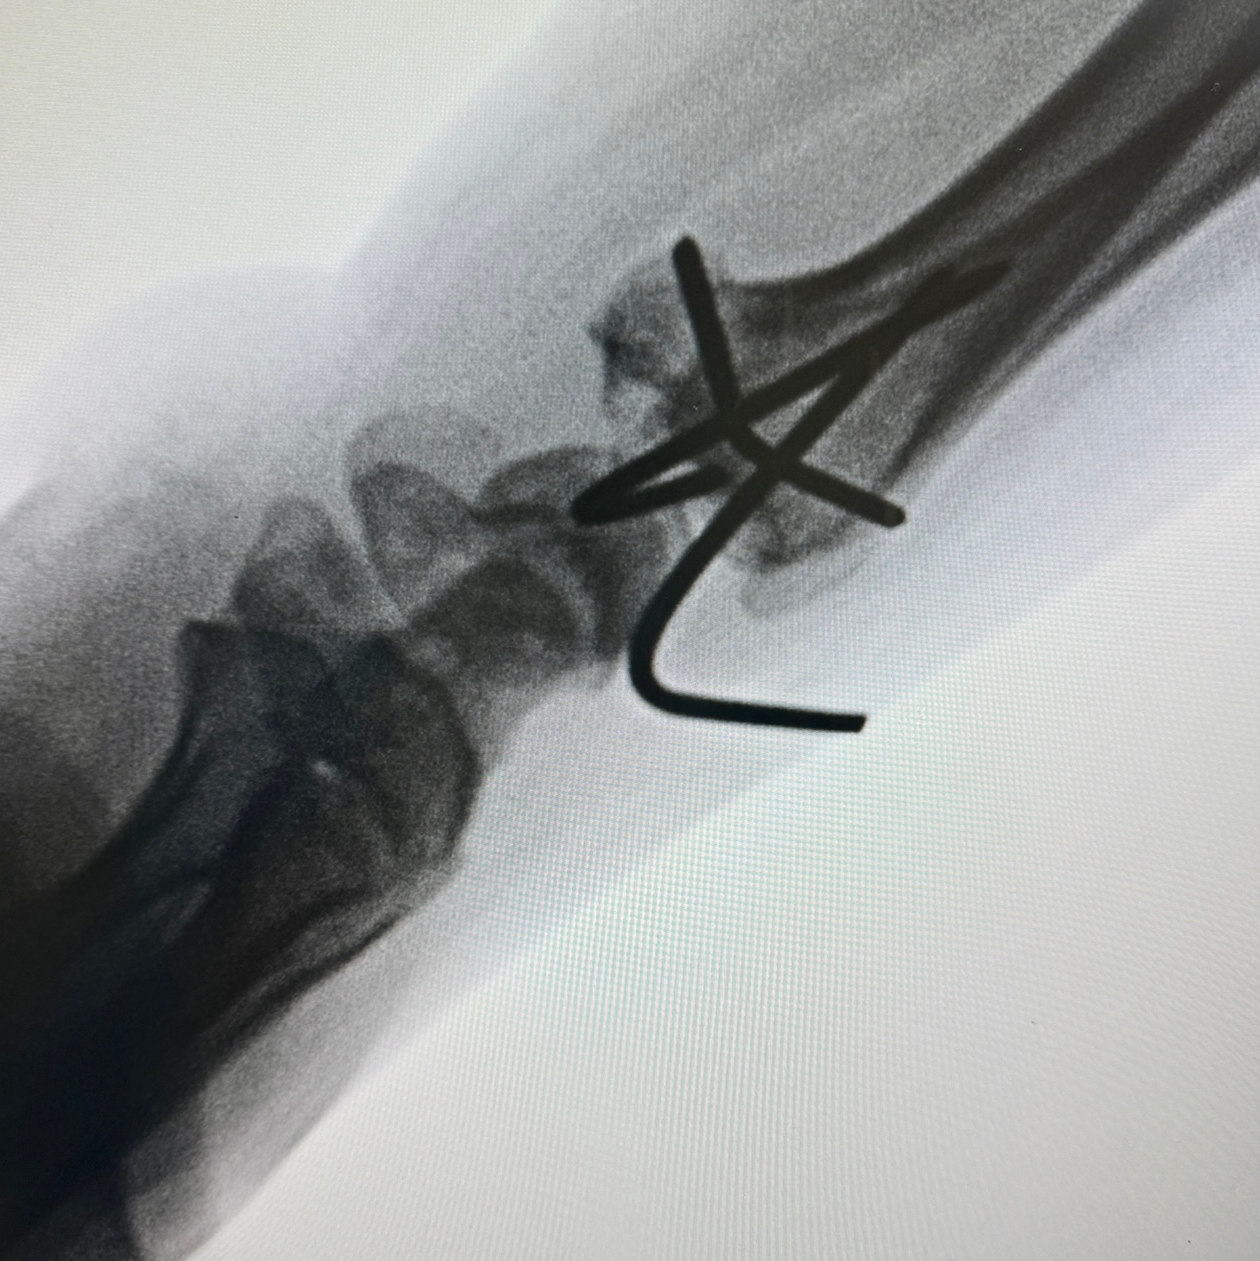

Distal end radius fracture of young patient operated with. Closed reduction and K wire fixation